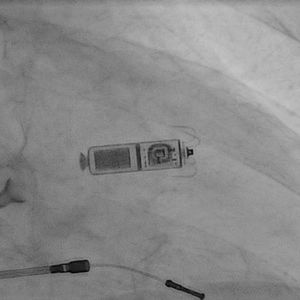

Kardiologen der Universitätsmedizin Greifswald haben im Januar die ersten kabellosen Herzschrittmacher, die Micra-Kardiokapsel des Medizintechnik-Unternehmens Medtronic, eingesetzt. Das Medtronic Micra Transcatheter Pacing System, kurz Micra, ist der kleinste Herzschrittmacher der Welt.

„Die 25,9 mm große Kardiokapsel ist weniger als ein Zehntel so groß wie ein herkömmlicher Schrittmacher und etwa so groß wie eine große Vitamintablette. Sie bietet die fortschrittlichste Herzschrittmachertechnologie und ist dabei kosmetisch unsichtbar und klein genug, so dass wir sie über einen Katheter minimalinvasiv unmittelbar ins Herz einbringen können“, erläuterte Busch.

Stattdessen wird das System mit winzigen Titanärmchen in der Herzwand verankert und gibt über einen Pol an der Spitze des Geräts die elektrischen Impulse für die Herzaktivität ab. Trotz der geringen Größe der Kardiokapsel beträgt die geschätzte Lebenszeit der Batterie zehn Jahre. Die Micra Kardiokapsel ist für Patienten vorgesehen, die ein Einkammerstimulationssystem benötigen.